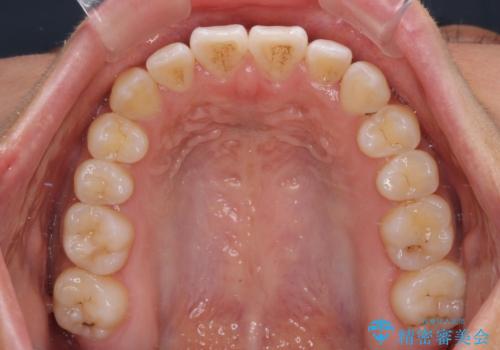

- 前歯の開咬と、上顎前歯の八重歯やデコボコを気にして来院された患者様です。

上顎歯列が狭窄していたため、急速拡大装置により上顎骨を側方に拡大し、その後ワイヤー装置にて矯正治療を行うこととしました。

急速拡大装置で上顎骨を十分に拡大できたことで、非抜歯で八重歯を歯列に納めることができました。